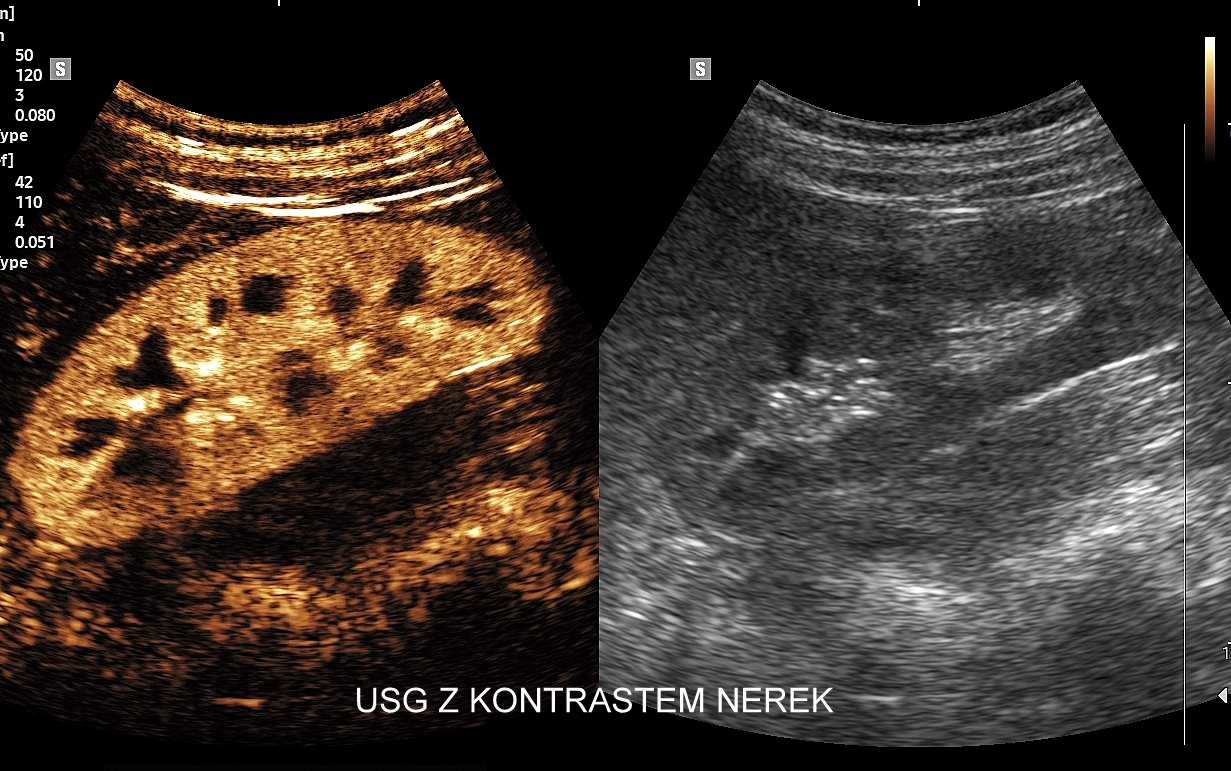

Badanie USG z kontrastem, z języka angielskiego CEUS (contrast enhanced ultrasound), jest badaniem ultrasonograficznym, podczas którego, zwykle dożylnie, podaje się specjalny kontrast w celu uwidocznienia struktur narządowych oraz tkanek, które niewystarczająco wyraźnie są widoczne lub charakteryzowane w klasycznym badaniu USG, a nawet w innych badaniach obrazowych jak tomografia komputerowa (TK) czy rezonans magnetyczny (MRI).

Strukturę kontrastu do USG stanowią mikropęcherzyki o wielkości <10 μm zbudowane z osłonki lipidowej, w której zamknięty jest neutralny gaz heksafluorek siarki (SF6). Mikropęcherzyki po podaniu dożylnym przedostają się mikrokrążenia narządów i są w nich wykrywane za pomocą obrazowania USG specjalnie do tego przystosowanym aparatem. Oprócz dożylnego podawania kontrastu, w przypadku niektórych wskazań, może być on także administrowany dopęcherzowo.

Narządem, w którego diagnostyce najczęściej wykorzystuje się CEUS, jest wątroba; w dalszej kolejności nerki, trzustka, protezy naczyniowe aorty, drogi żółciowe oraz inne narządy wewnętrzne.

Badanie USG z kontrastem najczęściej wykorzystuje się do oceny zmian ogniskowych w wątrobie, potocznie nazywanych guzami wątroby, z których wiele ma na tyle specyficzny obraz mikrounaczynienia w obrazowaniu CEUS, że możliwe jest uniknięcie konieczności badania obciążającymi metodami TK lub MRI. Badanie CEUS w przeważającej większości pozwala odpowiedzieć, czy zmiana ogniskowa wątroby ma cechy złośliwe czy łagodne. Dodatkowo CEUS jest pomocny do wykrywania przerzutów do wątroby pochodzących z nowotworów w innej lokalizacji. W przypadku przerzutów o wielkości mniejszej niż 1 cm CEUS ma większą czułość aniżeli badanie TK.